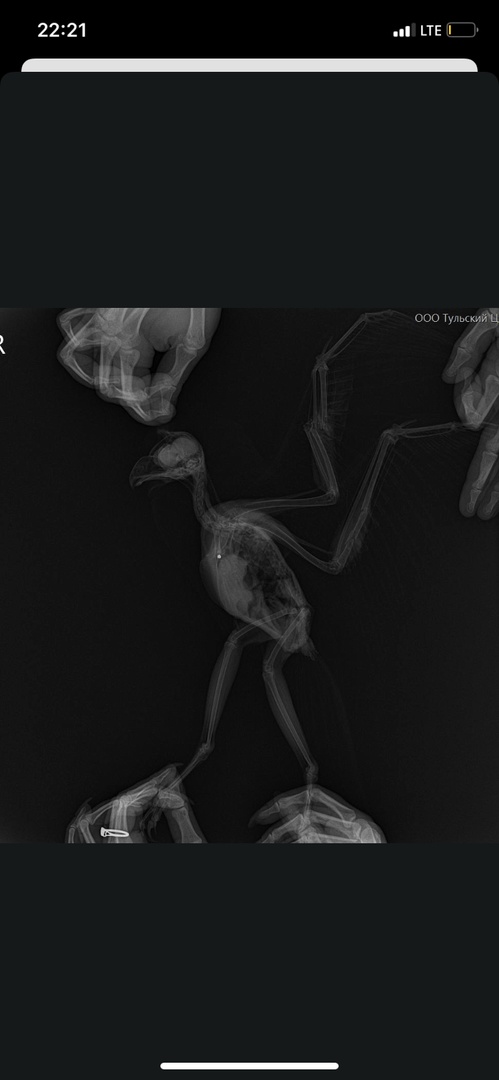

Сначала подумали, что птицу сбила машина. Но рентген показал дробь в верхней области груди.

На правом крыле сломаны локтевая и лучевая кости, и оно болтается. Левое крыло пострадало меньше. В целом птица немного отстает в весе, но ведёт себя активно.